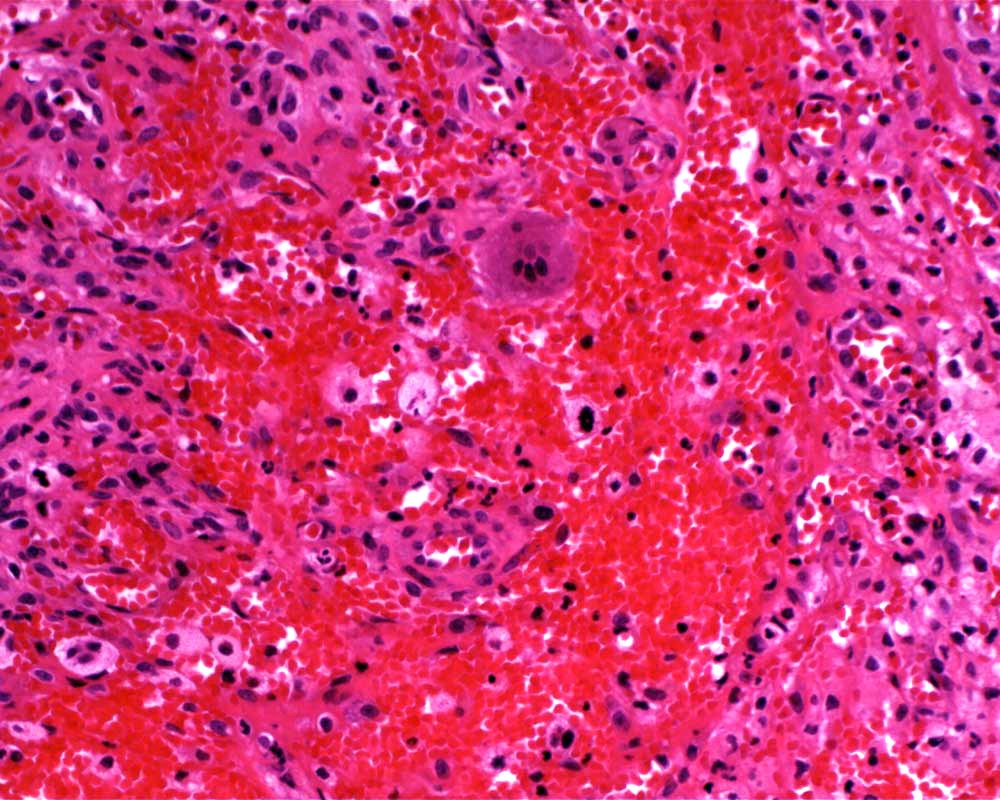

Case: FemurLesion

Final Diagnosis: